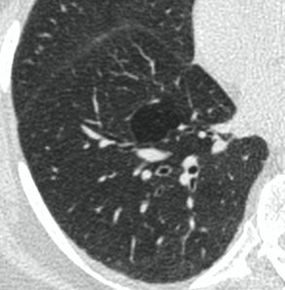

Методы лучевой диагностики применяют для выявления COVID-19 пневмоний, их осложнений, дифференциальной диагностики с другими заболеваниями легких, а также для определения степени выраженности и динамики изменений, оценки эффективности проводимой терапии.

КТ имеет высокую чувствительность в выявлении изменений в легких, характерных для COVID-19. Применение КТ целесообразно для первичной оценки состояния ОГК у пациентов с тяжелыми прогрессирующими формами заболевания, а также для дифференциальной диагностики выявленных изменений и оценки динамики процесса. КТ позволяет выявить характерные изменения в легких у пациентов с COVID-19 еще до появления положительных лабораторных тестов на инфекцию с помощью МАНК. В то же время, КТ выявляет изменения легких у значительного числа пациентов с бессимптомной и легкой формами заболевания, которым не требуется госпитализация. Результаты КТ в этих случаях не влияют на тактику лечения и прогноз заболевания при наличии лабораторного подтверждения COVID-19. Поэтому массовое применение КТ для скрининга асимптомных и легких форм болезни не рекомендуется.

15. Рекомендации по формированию описаний и оценке изменений в легких и ОГК при имеющейся/подозреваемой пневмонии COVID-19 представлены в Приложении 1.